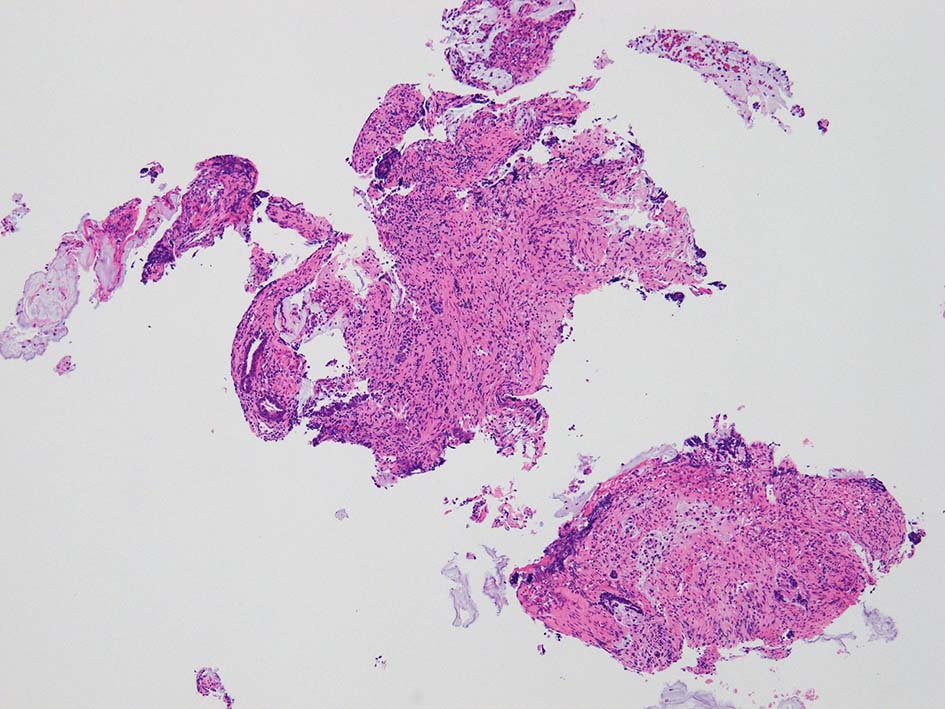

IWT 76 year-old male. 尿管結石, 結石性腎盂腎炎で治療している.

膀胱鏡検査で頸部6時方向に乳頭状腫瘤があり, 膀胱がん疑いで生検をおこなう.

腸管型の腺癌。大腸の高分化腺癌と組織学的に区別は難しい.

desmoplastic fibrosis, 粘液浸潤のみられる組織片にはsig, porのadenocarcinoma浸潤が確認される.